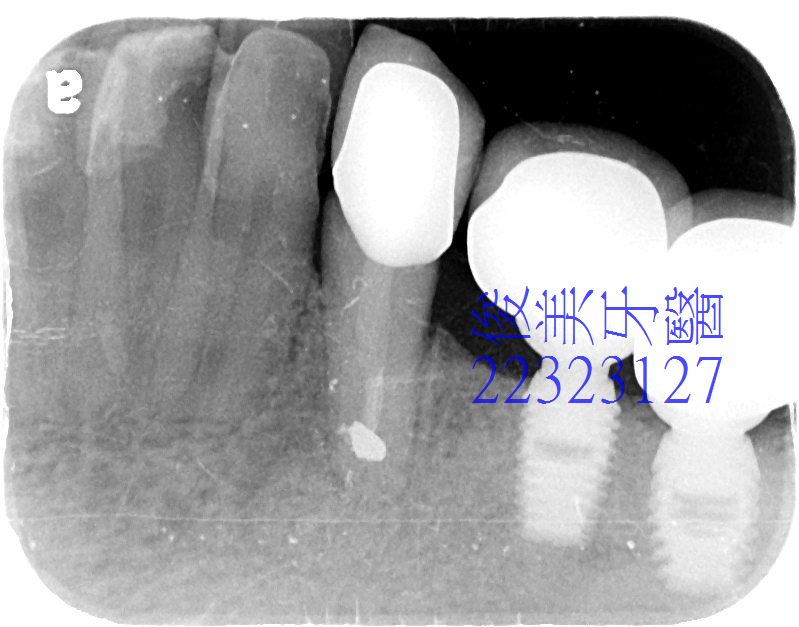

患者多年前抽過神經的牙齒,有病灶,牙根尖底部有病變,檢查時皆有提醒患者注意,直到近期,口腔內出現小腫苞,

牙根周圍黑影已消失, 出現白色的骨粉顆粒狀,如此可避免囊腫惡化,患者需強力冰敷3天,3個月內暫勿咀嚼這區,